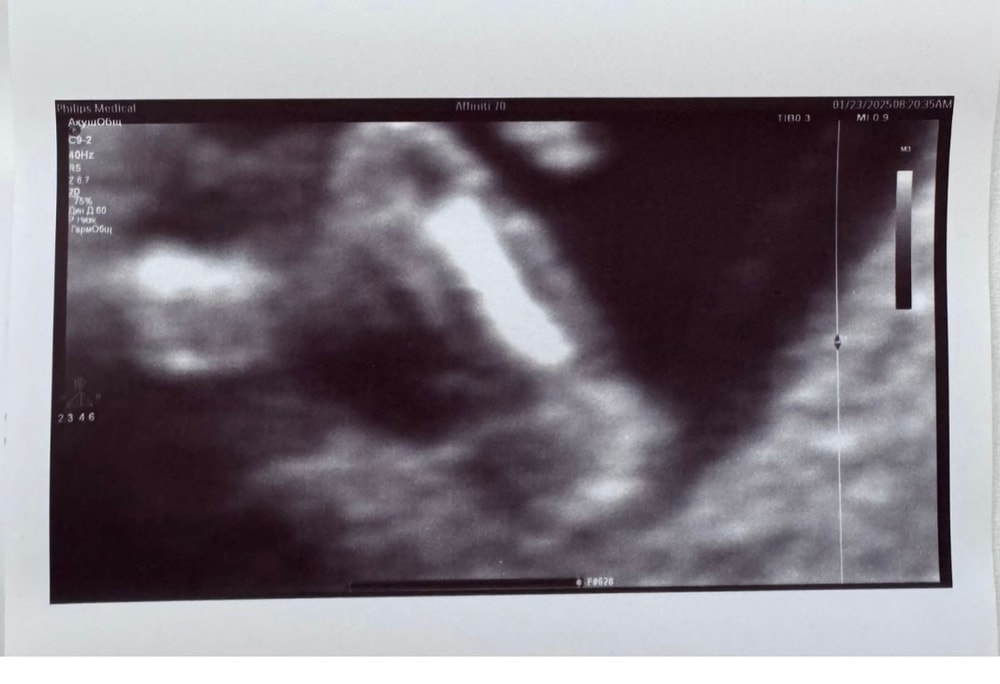

Мне одна и та же узист делала скрининги с тремя последними беременностями. В прошлые разы точно определяла мальчишек в 12 недель, причем смотрела не сбоку половой бугорок, а именно между ножек. Я думала тогда что она просто угадала. И в этот раз она так же между ножек смотрела, и сказала что ничего мальчишеского не видит, что скорее всего девочка. Я конечно не поверила, ну думаю как можно на таком сроке что то между ножек разглядеть, когда в статьях пишут что на этом сроке у них там все якобы одинаково. Но позже нам подтвердили девочку, и на узи, и по НИПТу. Вот фото третьего сына между ножек: Изображение А вот у дочки на таком же сроке 12 недель: Изображение